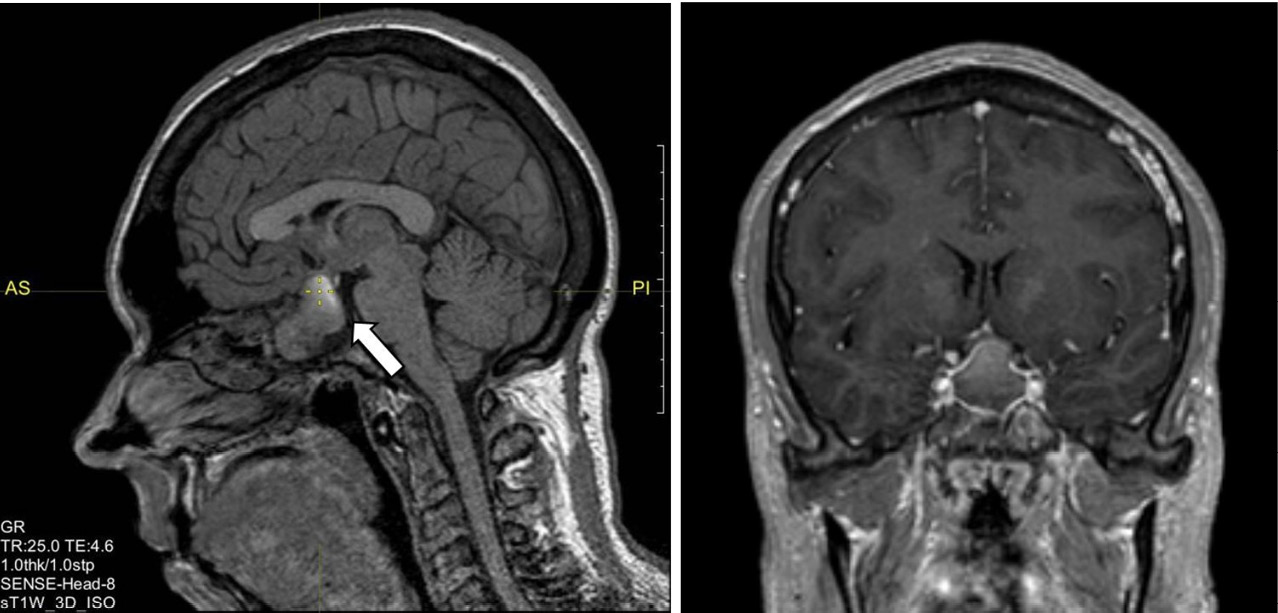

Клиническое наблюдение

Рис. 1. Магнитно-резонансная томография гипофиза с контрастным усилением, Т1-взвешенные изображения. Визуализируется макроаденома гипофиза с супра-, инфра-, латероселлярным ростом с кровоизлиянием (указана стрелкой)

В феврале 2021 г. находилась на госпитализации в ГНЦ РФ ФГБУ «НМИЦ эндокринологии» Минздрава России. Верифицирован диагноз акромегалии по данным СТГ > 1 нг/мл в ходе ОГТТ (см. табл. 1) и с учетом характерной клинической симптоматики при нормальном уровне ИФР-1 – 202,4 нг/мл (51–271). По данным МРТ от 17.02.2021 визуализирована аденома гипофиза с кровоизлиянием размерами 16,5 × 20 × 23 мм с супра-, инфра-, антеселлярным ростом, размеры которой уменьшились по сравнению с результатом от декабря 2020 г. Пациентка консультирована нейрохирургом – рекомендовано трансназальное нейрохирургическое лечение. Одновременно был подтвержден папиллярный рак щитовидной железы с метастазами в региональные лимфоузлы. Первым этапом лечения рекомендовано проведение хирургического лечения папиллярного рака щитовидной железы. В связи с нецелевыми значениями св. Т4 на фоне приема 75 мкг левотироксина (св. Т4 13,55 пмоль/л (9–19)) доза препарата была увеличена до 100 мкг в сутки.